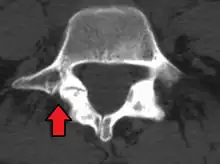

Anterolisthesis L5/S1

Anterolisthesis L5/S1. Blue arrow normal pars interarticularis. Red arrow is a break in pars interarticularis